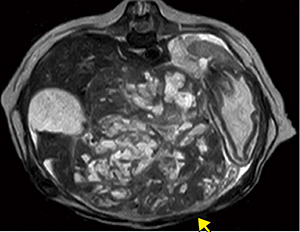

■症例4:イヌ,肝臓がん

膝コイル,T2WI,AXI,FOV:200mm,

TR/TE:3900/95,スライス厚:3mm,

マトリックス:288×224,scan time:5:48